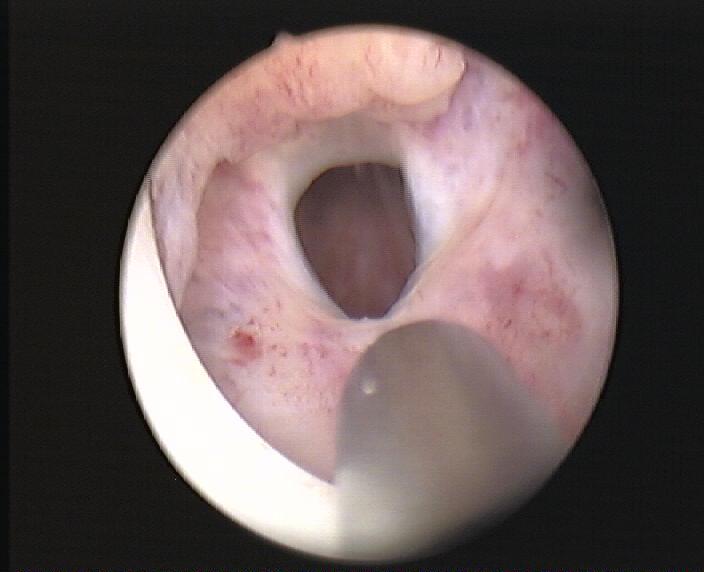

| Incisione endoscopica laser di stenosi del collo vescicale | |||||||||